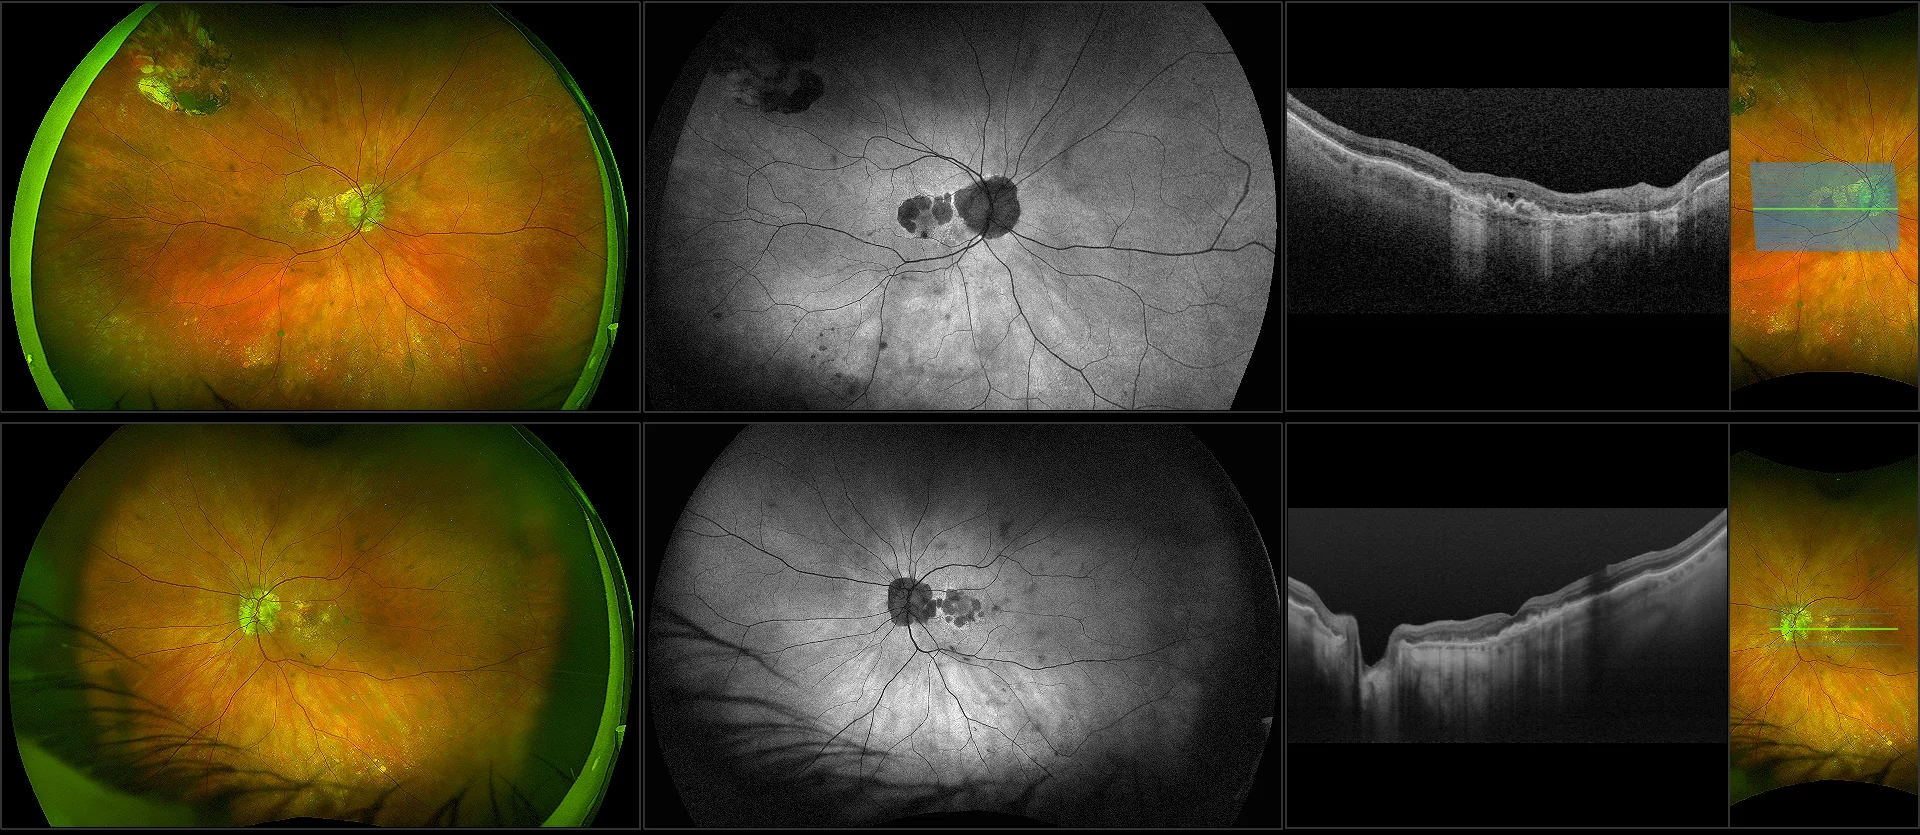

Multimodal optomap Images Enhance the Management of AMD

optomap has helped re-define AMD as a pan-retinal disorder.

optomap Multimodal AMD Cases

Optos offers multimodal imaging with all ultra-widefield devices. Having both ultra-widefield and four images captured in less than one second has been shown to enhance pathology detection and disease management as well as improve practice and clinic flow. Ultra-widefield multimodal imaging is important across all access points of patient care - screening, detection, diagnosis, and treatment.